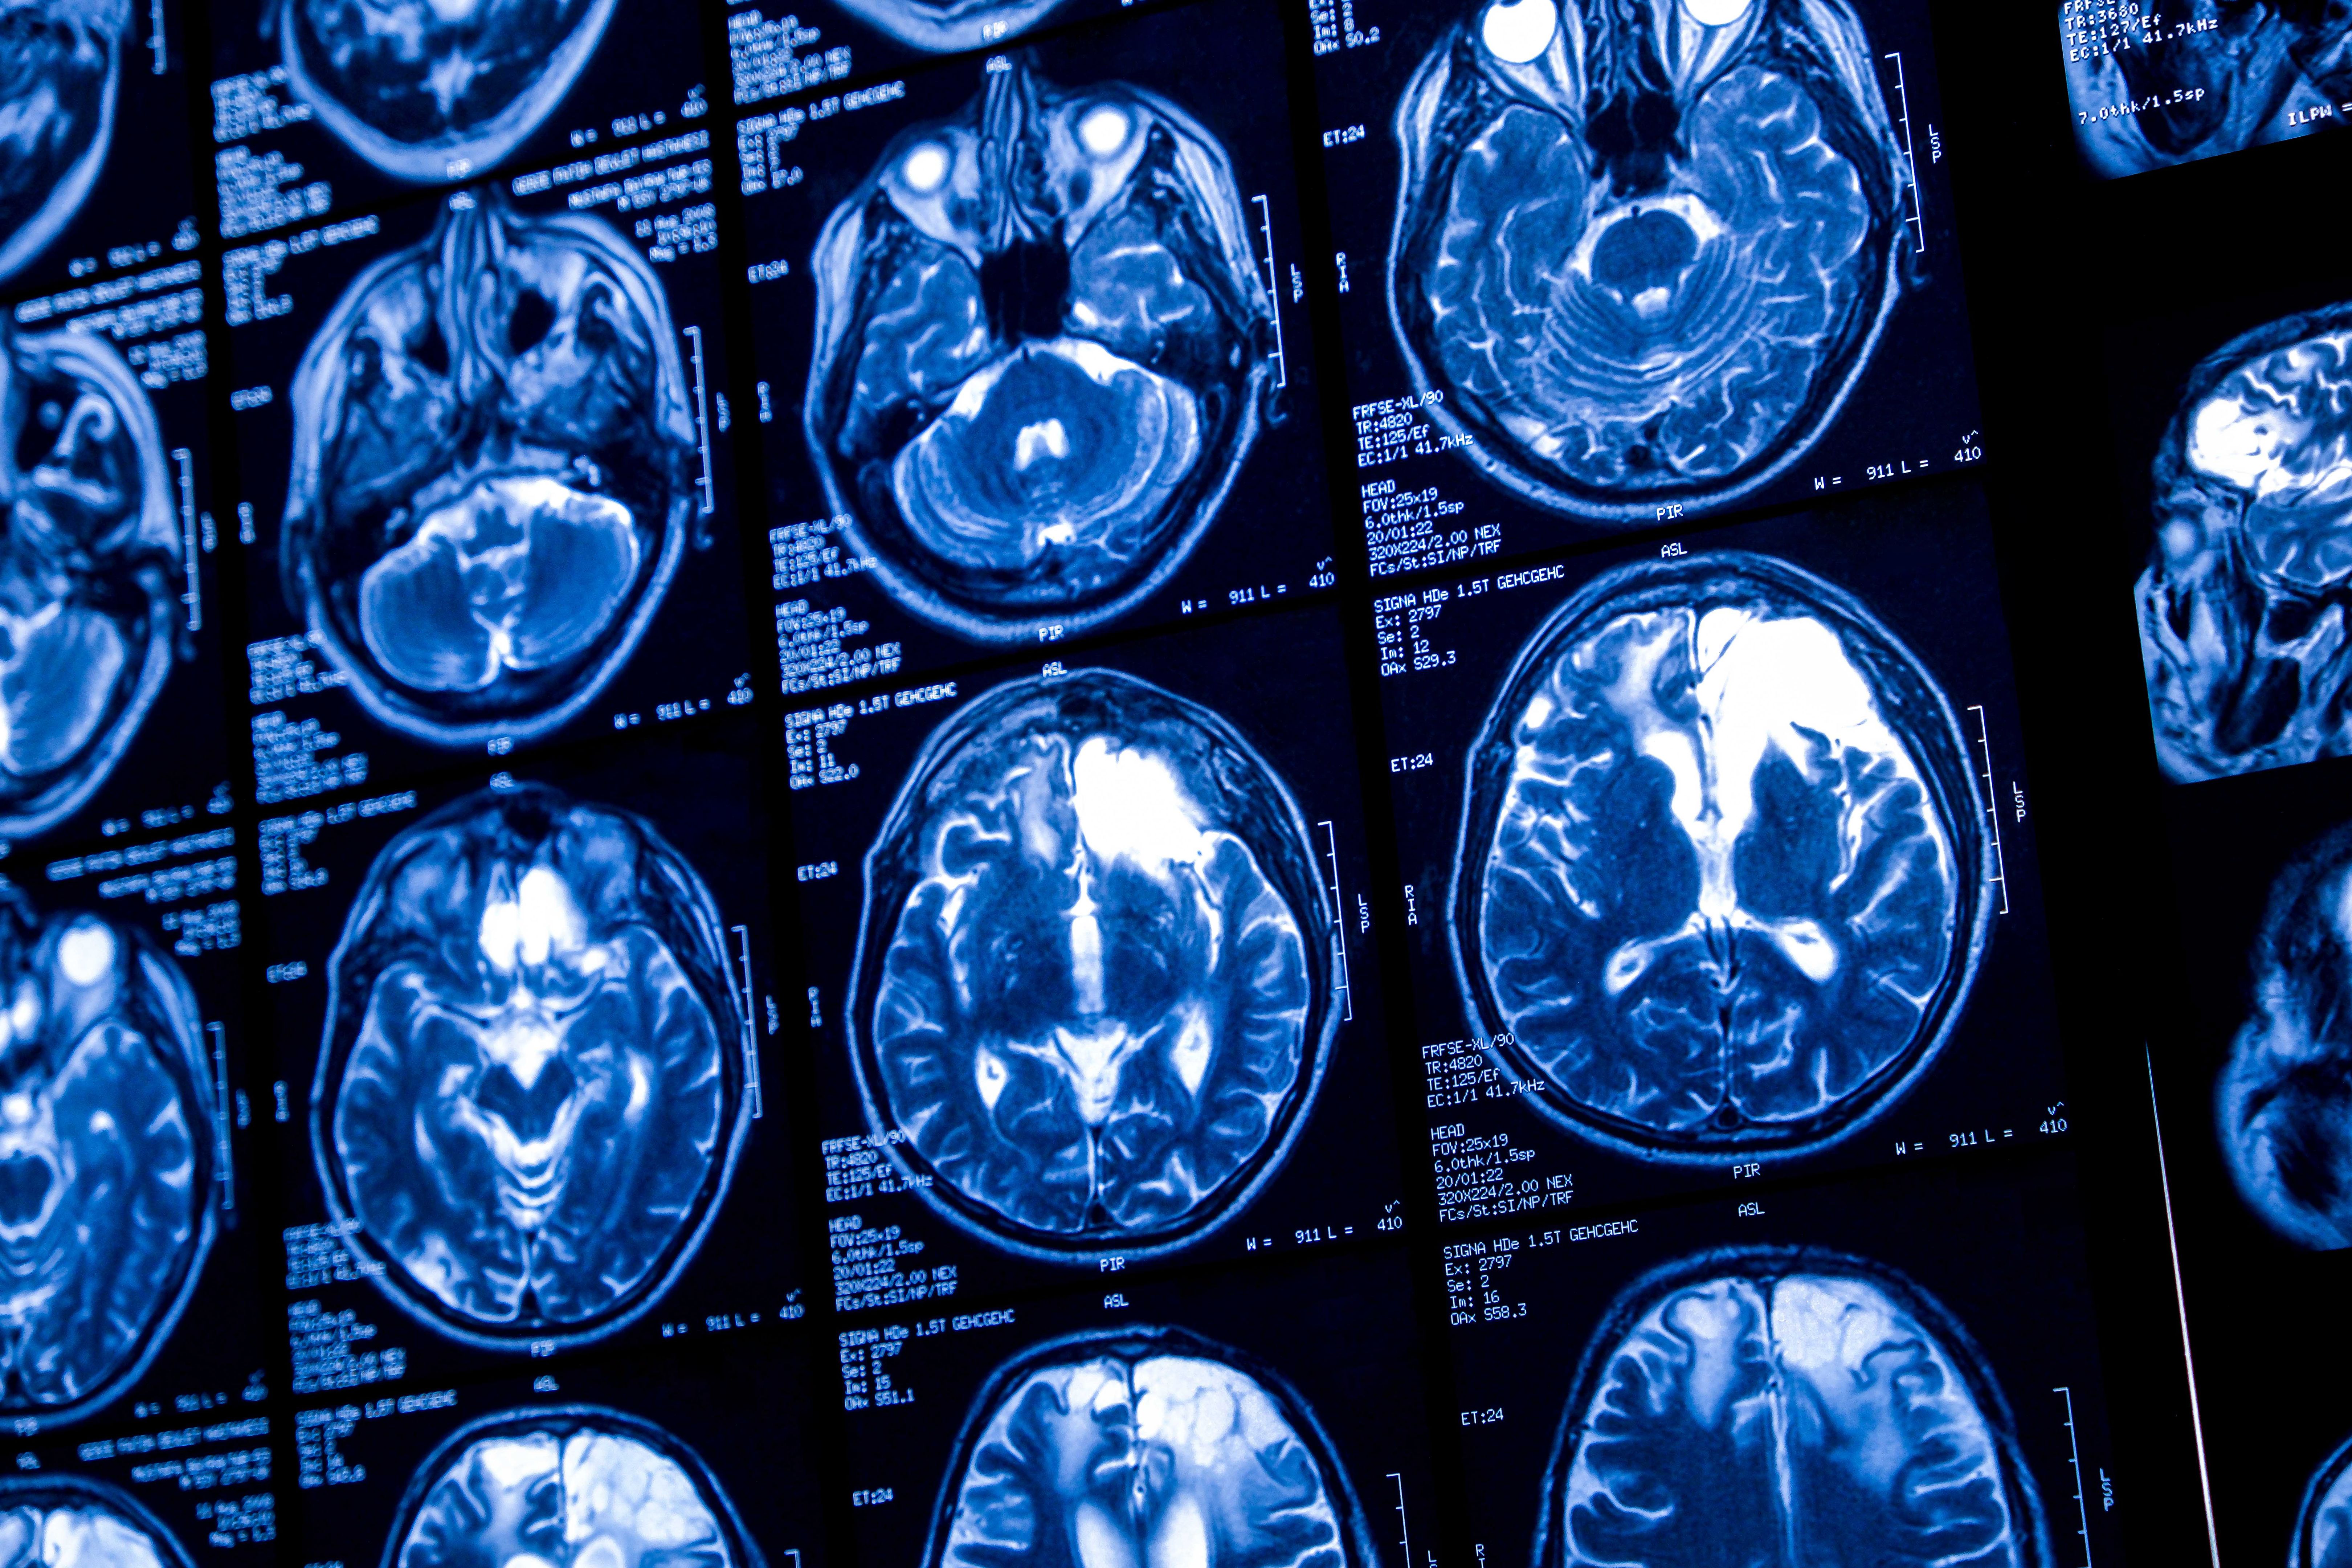

Una de las razones por las que las adicciones son llamadas enfermedades es porque afectan el cerebro y el comportamiento de manera similar a otras enfermedades médicas. La repetida exposición a la sustancia o actividad adictiva cambia la estructura y función del cerebro, dificultando la capacidad de la persona para tomar decisiones saludables. La persona no tiene la intención de desarrollar una adicción, esta de va instalando de forma progresiva a pesar de las consecuencias que acompañan las conductas de consumo.

Las adicciones afectan áreas del cerebro relacionadas con el placer, el control y la toma de decisiones. Estas áreas incluyen la corteza prefrontal y el sistema de recompensa. Al consumir una sustancia, el cerebro libera dopamina, un neurotransmisor que genera sensaciones de placer. Con el tiempo, el cerebro se adapta y necesita más de la sustancia para obtener el mismo efecto, lo que lleva a la dependencia.

Este cambio en el cerebro es similar al que ocurre en otras enfermedades crónicas, como la diabetes o la hipertensión, donde el cuerpo deja de funcionar correctamente sin tratamiento. Esto refuerza la idea de que la adicción es una enfermedad que requiere atención médica y tratamiento especializado.